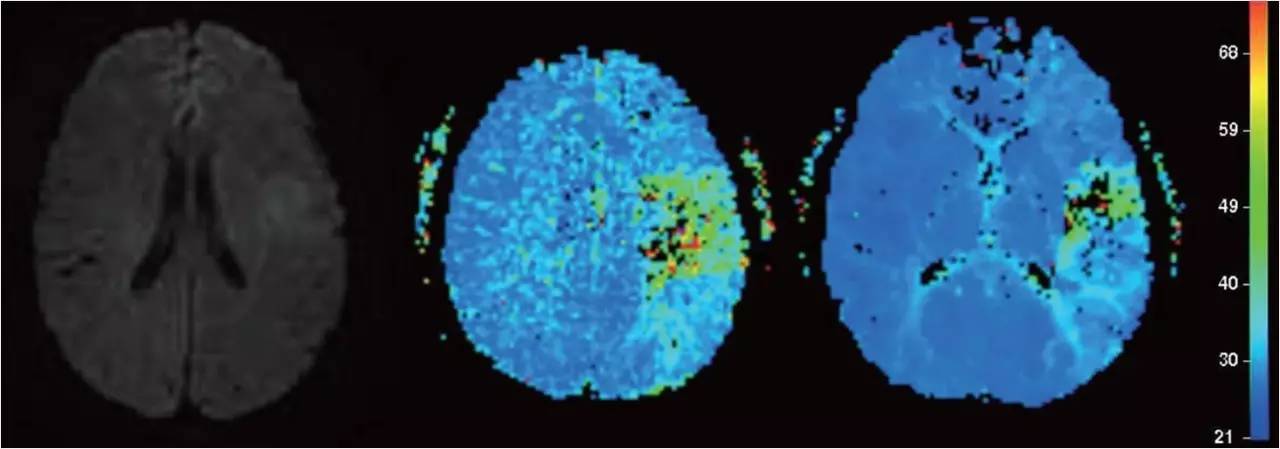

》男性,47岁,SIE;

》UCG:主动脉瓣关闭不全,赘生物;

》突发言语不能、右侧肢体活动不能;

》查体:运动性失语,右侧肌张力低,右侧肌力0级,右侧巴氏征阳性 。NIHSS评分18分;

》CT:颅内未见出血;

》DSA:左侧大脑中动脉闭塞。

术后

》意识清楚,言语流利,四肢活动自如;

》四肢肌力Ⅴ级;

》术后24小时NIHSS评分:0分;

》5天后主动脉换瓣术;

》90天mRS评分0分。